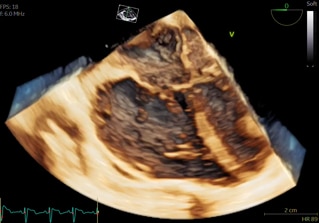

9VT-D gives you access to real-time multiplane and 4D imaging to help improve diagnostic and procedural confidence in patients as small as 5 Kg. Get clear and realistic visualizations of pediatric heart structures with 4D color flow analysis.

9vt-d-proble-4d-volume-ci-en